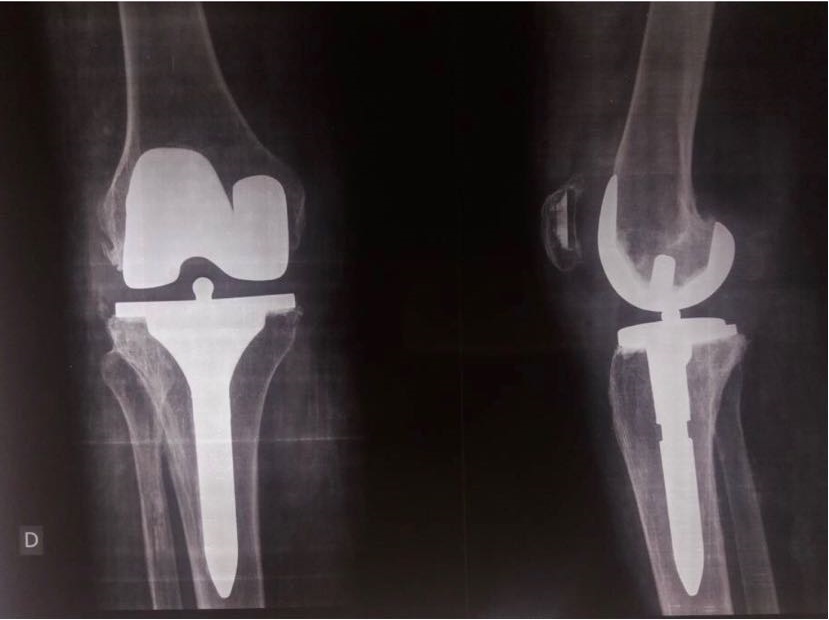

2- PTG postero-stabilisee cimentée avec quille tibiale longue